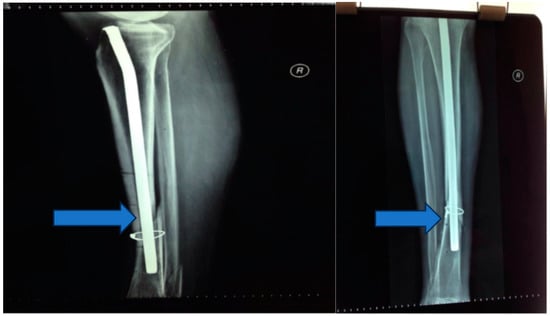

Stage 1: initial stabilization and osteosynthesis (Figure 1).

Objective: To provide immediate stabilization of the open tibial fracture and initiate the process of bone fixation.

Methods: The patient underwent external fixation in the emergency room.

Seven days postinjury, an osteosynthesis procedure was performed, involving the placement of a Kuntscher nail and wire cerclage (Figure 2 and Figure 3).

Figure 1. (A,B) External fixation in the emergency room.